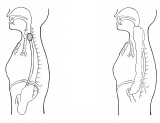

前頚部展開法最新モデル2006

胸襟を開き合える仲間は貴重ですね。